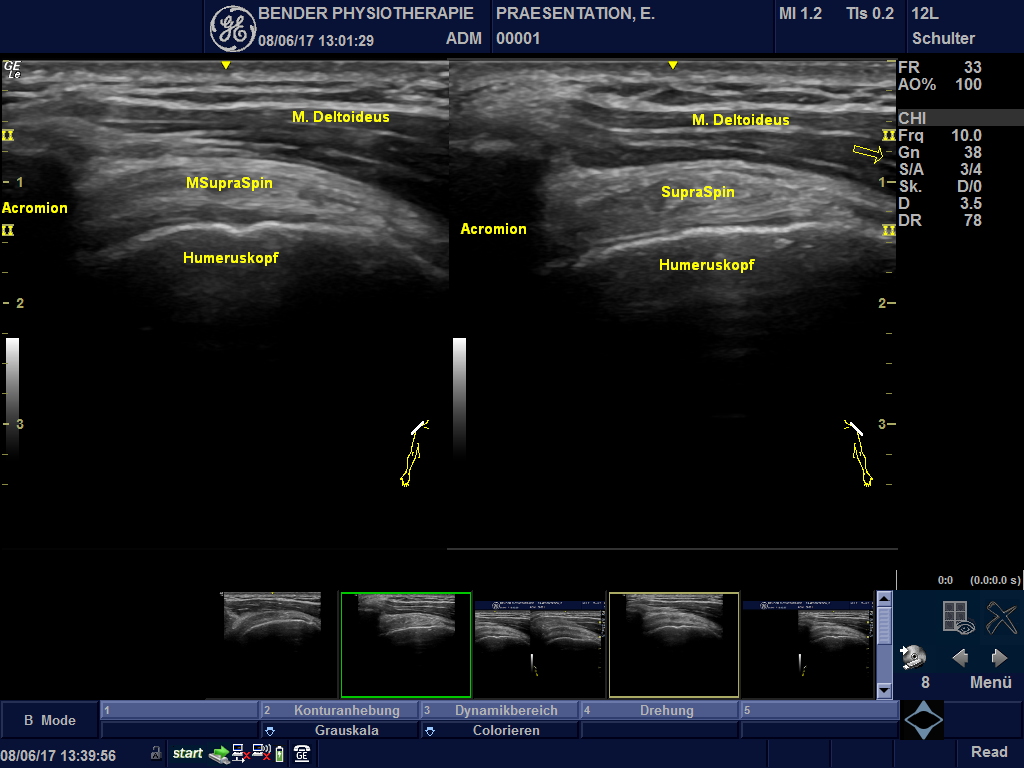

Ultraschalldiagnostik:

Spürbares sichtbar machen

Bildgebender Ultraschall in der Physiotherapie: Der muskoskelettale Ultraschall eröffnet unserer Physiotherapie Praxis spannende neue Dimensionen.

Mit dem „Real Time Scanning“ - Verfahren können wir Ihrer Problematik näher auf den Grund gehen.

• Impingement-Syndrome